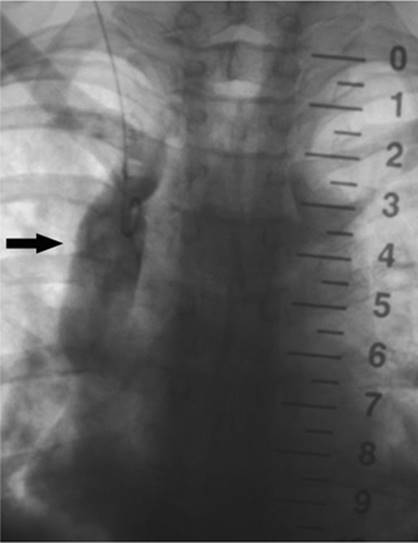

000159

Figure 35.5. A 19-year-old patient with sepsis and cough. A: Axial CT at the level of the midchest demonstrates an 8.5-cm fluid collection in the right posterior hemithorax (asterisk) with compression atelectasis of the adjacent lung. Direct percutaneous access is blocked due to inferior margin of the scapula, overlying ribs, and aerated lung. B: Patient was placed in a left-side-down decubitus position. Change in position provides direct posterior access to the fluid collection. A localizer grid has been placed to mark site of access. C: Access gained with micropuncture needle system and then a 14 Fr drain placed over a wire. Fluid aspirated with syringe and then drain was secured in place and connected to suction bulb. D: Postdrain placement CT. (Case courtesy of Lauren Alexander, MD, Gainesville, FL.)